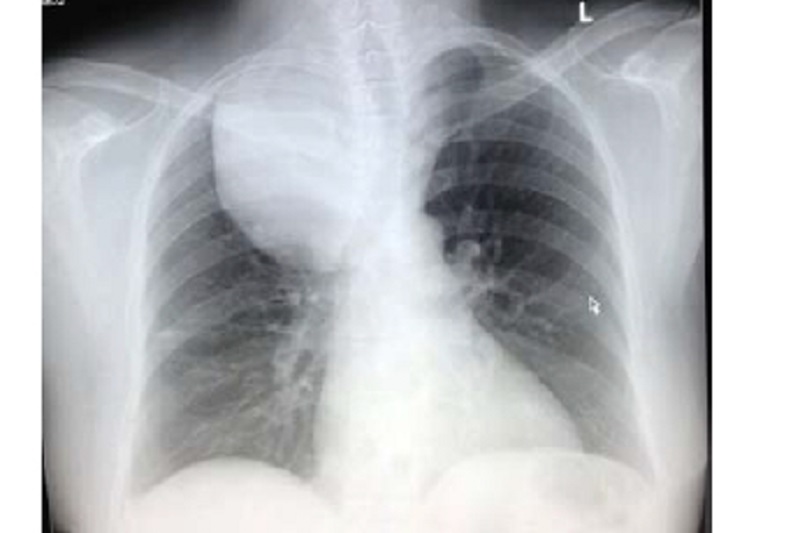

X - quang lồng ngực hoặc cắt lớp vi tính, cộng hưởng từ vùng ngực: được dùng trong trường hợp có nghi ngờ bướu giáp trong lồng ngực. X - quang có thể cho thấy có hay không bướu giáp trong lồng ngực và bướu giáp có chèn ép vào khí quản hay không. Còn để đánh giá mức độ bướu cổ cũng như ảnh hưởng của nó đến các cơ quan xung quanh, chụp cắt lớp vi tính hoặc cộng hưởng từ sẽ mang lại nhiều thông tin hữu ích hơn. Tuy nhiên cần lưu ý, các trường hợp bướu giáp, nếu chụp có tiêm thuốc cản quang cần được đánh giá và lưu ý kĩ, do trong thuốc cản quang có chứa một lượng lớn iod.

Hình ảnh bướu giáp trong lồng ngực trên phim x-quang